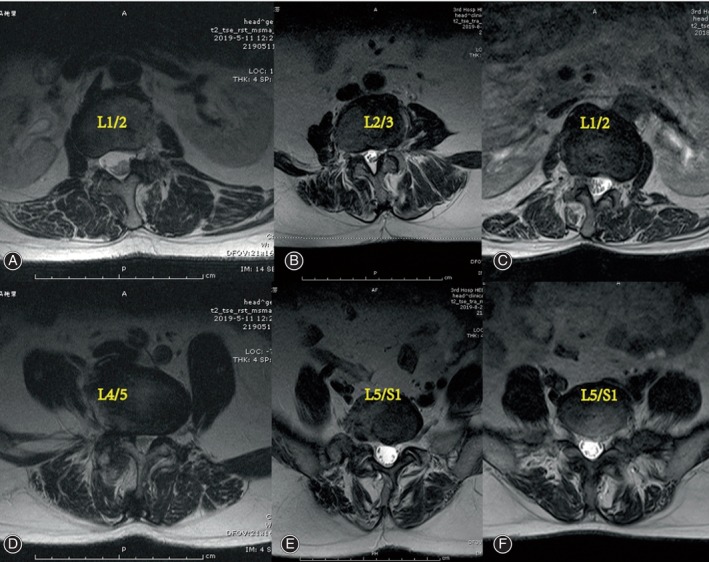

The cross‐sectional areas (CSAs) of the MS and ES muscles at the apex of the primary and fractional curves were determined by tracing the muscle’s fascial boundary using Image J‐win64 software.ref. os14185-bib-0025 To evaluate fat infiltration, the fat infiltration area (FIA) within the total CSA of both muscles was quantified using a threshold technique.ref. os14185-bib-0026 Subsequently, the percentage of fat infiltration area (%FIA) relative to the total CSA was calculated (Fig. 2). The central image, corresponding to the apical vertebra, was selected for PM assessment (Fig. 3). The convex side encompassed both the primary curve’s convex side and the compensatory curve’s convex side, with the difference value between the concave and convex sides indicating the degree of asymmetric PM change. We defined the difference of more than 3% between concave and convex paravertebral muscle fat infiltration as asymmetrical threshold. Paravertebral muscle parameters and imaging parameters were measured respectively by two observers independently, blinded to the patients’ characteristics.